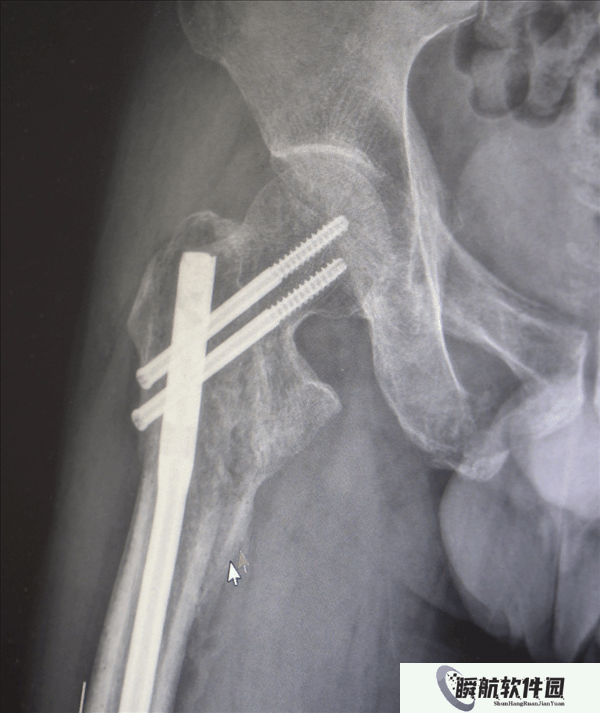

创伤性失血性休克、多发性肋骨骨折、肺部损伤、右侧肩胛骨粉碎骨折、右侧肱骨髁上开放粉碎性骨折、右股骨粗隆及股骨干粉碎性骨折、骨盆粉碎性骨折、腰椎横突多发骨折、腰骶柱神经损伤、臂丛神经损伤、胸腔积液、腹腔积液等。

经医生检查,张先生全身共有六处较大骨折部位,多为严重粉碎性骨折,全身骨折碎块达30多块!